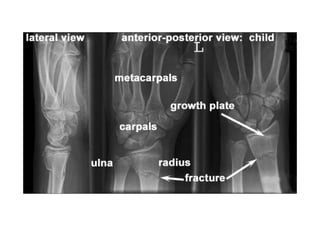

RADIOLOGIA DO

TRAUMA DO ESQUELETO

Referência: http://www.accessexcellence.org/RC/VL/